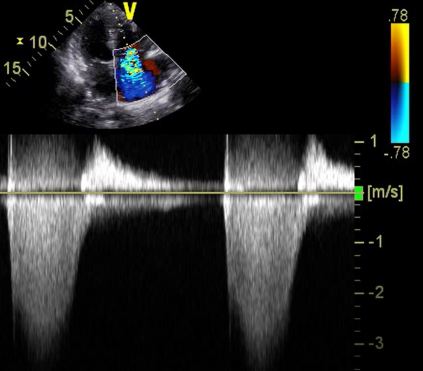

TRVMax on this view was 2. That’s not too bad. Or is it?

Below is a flipped view of the heart (TV on the right of screen). The alignment of the probe is more inline with the TR Jet.

Here we appreciate the importance of the doppler plane being inline with the flow of blood.